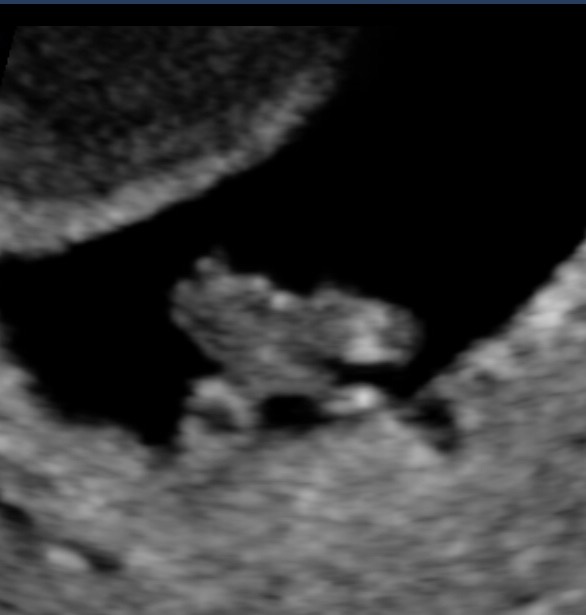

This baby looks chill to me, kicking back with their feet up